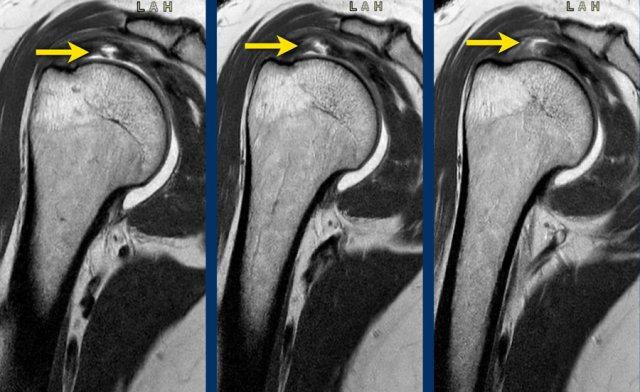

Đôi khi có thể khó phân biệt rách một phần với rách toàn bộ chiều dày.

Khi nhìn vào hình ảnh đầu tiên, tổn thương trông giống như rách một phần chiều dày phía mặt khớp.

Tuy nhiên, trên các lát cắt tiếp theo của chụp MRI khớp có thuốc tương phản từ, có thể thấy sự lan rộng không đều của thuốc tương phản từ từ mặt khớp ở bên trái đến mặt túi hoạt dịch ở bên phải, xác nhận đây là rách toàn bộ chiều dày.